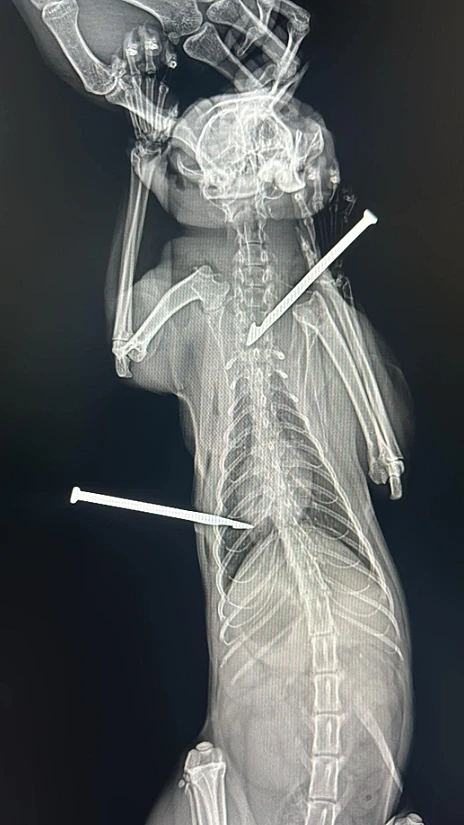

אמיץ החתול | צילום: GingerPet Station

סלסון ורונה פסקואה, בני זוג מהעיר ג'נרל סנטוס שבפיליפינים, מצאו בשירותים של מסעדת מזון מהיר חתול שחור עם שני חצי מתכת שנעוצים בחזהו.

הם לקחו את החתול לחנות חיות מחמד שהעבירה אותו לאחר מכן לבית חולים לחיות, שם עבר ניתוח מיידי להסרת חיצי המתכת.

החיצים חדרו ליד ריאותיו והיה חשש מיידי לחייו. הווטרינר שטיפל בחתול סיפר שהחתול ספג קרעים בשריר הבין-צלעי. למרבה המזל, הניתוח עבר בהצלחה והחתול נמצא בימים אלה בהחלמה.